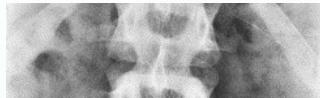

Open-Mouth View

- For C1 and C2

- Odontoid fractures

- Lateral mass fractures

- Look for:

- Symmetry

- Continuity of bone